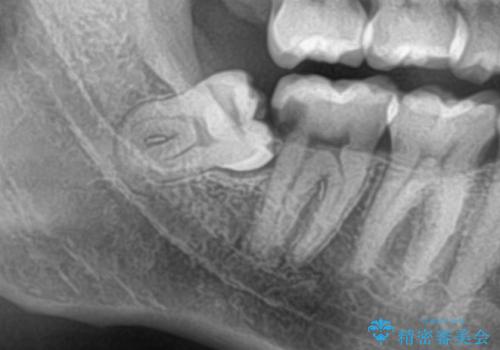

斜めに生えてきている親知らずを抜きたい

- 親知らずが虫歯になっている気がするとの事で来院。

親知らずとその手前の歯が虫歯になっていました。

先に虫歯を徹底的に取り除き親知らずを抜歯してe-maxインレーで治療を行いました。